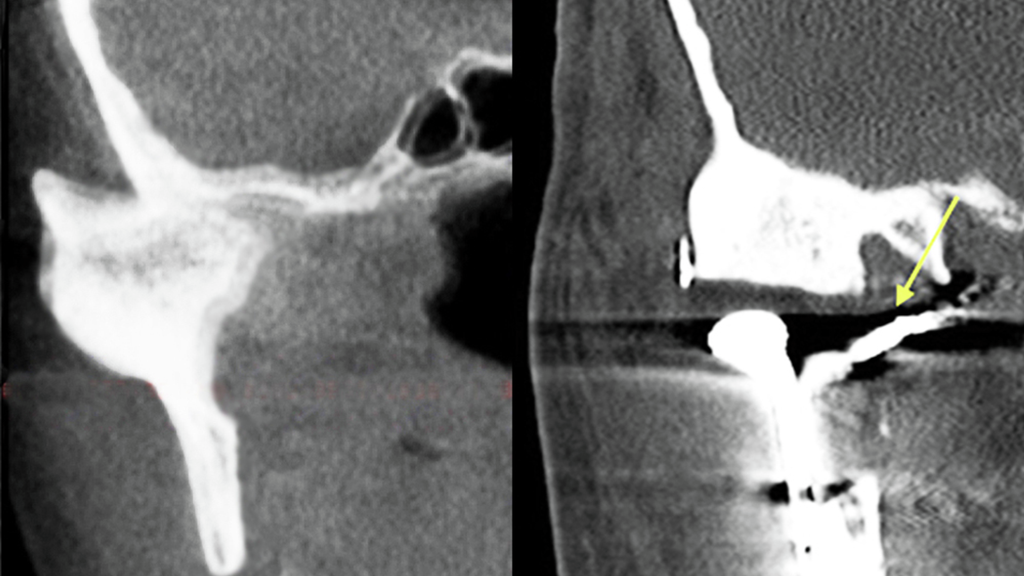

Skull x-ray shows complete blockage of the internal maxillary artery near the temporomandibular joint

Figure 1: Post-procedure film demonstrating successful embolization on the internal maxillary artery medial to the ankylotic mass.

The day before surgery, Mr. W had a percutaneous embolization procedure on his left internal maxillary artery under continuous fluoroscopic guidance, with post-embolization angiography demonstrating exclusion of the artery at a segment medial and deep to the ramus of the mandible (Figure 1).